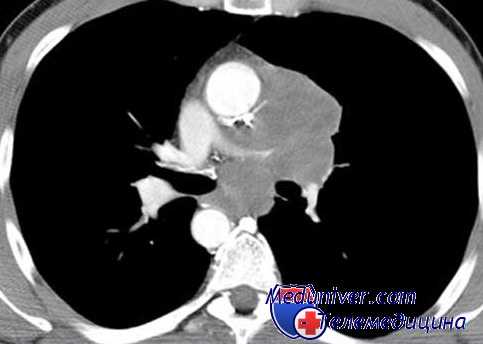

Рис. 1

Гранулематозный периодонтит

16-го зуба

Рис. 4

Гранулирующий периодонтит

12-го зуба

Рис. 2

37-го зуба

Рис. 5

11-го зуба

Рис. 3

Острый пульпит 36-го зуба

Рис. 6

21-го зуба

Рис. 7

Одним из достоинств композитных материалов, заявляемых фирмами-производителями, является простота в использовании в связи с отсутствием необходимости наложения изолирующих материалов в проекции пульпы зуба. Это положение взято на вооружение практикующими врачами, так как позволяет экономить время врача, средства клиники и давать лучшие эстетические результаты, особенно в больших полостях 3-го и 5-го классов, в сравнении с комбинированным применением прокладочного материала и композита. Действительно, применение изолирующего прокладочного материала заставляет врача считаться с его оптическими свойствами (цветом, прозрачностью, занимаемым объемом) и каким-то образом вносить коррективы в выбор цвета и опаковости используемого композита. Все это существенно усложняет и удлиняет работу врача, поэтому фирмы-производители рекомендуют применять адгезивную систему композитов непосредственно на дентин, утверждая, что образующийся гибридный слой и служит прокладкой, достаточно хорошо защищающей пульпу от действия пломбы. Однако наши многолетние клинические наблюдения показали, что отсутствие изоляции дентина при использовании адгезивных систем и фотокомпозитов при лечении витальных зубов в течение 6–12 месяцев приводит к некрозу пульпы и дальнейшему развитию гранулирующего или гранулематозного периодонтита. Особенностью течения этого процесса является отсутствие или слабая выраженность симптомов, предшествующих некрозу пульпы.

На наш взгляд, даже правильная работа с адгезивной системой (хорошая изоляция рабочего поля коффердамом, соблюдение вре-менного режима нанесения компонентов) не всегда является залогом успеха лечения. Мы предполагаем, что за 15–20 секунд экспозиции гидрофильные компоненты адгезива успевают достичь пульпы даже при неглубоких кариозных полостях и оказать свое токсическое воздействие. Дальнейшее отсвечивание приводит к полимеризации адгезива и образованию гибридного слоя на поверхности дентина. В литературе практически полностью отсутствуют данные о морфологическом состоянии клеток пульпы после применения адгезивов. Исследования, проведенные на нашей кафедре (В. В. Патюков, 2000) на крысах, свидетельствуют о тканевой инертности полимеризованной порции композита и выраженном токсическом действии неполимеризованного и недополимеризованного композита, причем наиболее выраженный некроз тканей наблюдается именно при действии неполимеризованного адгезива. Рентгенограммы, приведенные ниже, иллюстрируют наши клинические наблюдения.